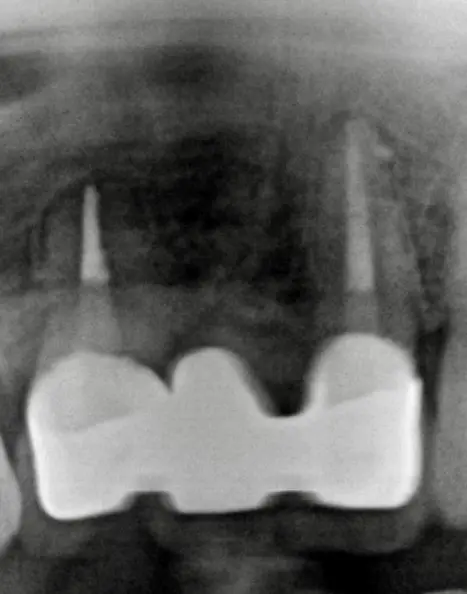

術中(ポイント試適)

レントゲン写真

孔はMTAセメントで封鎖しました

術後レントゲン写真

根管充填もMTAセメントによる穿孔封鎖もうまくいきました

術後2年後レントゲン写真

根の周りの黒い影がなくなり、骨もほとんど回復して、痛みもありません